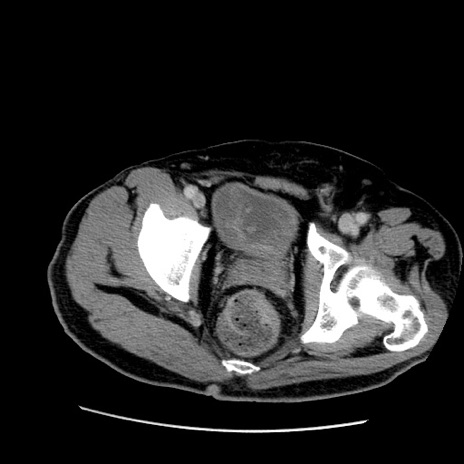

症例22(横断像)

【症例】50歳代男性

【主訴】腹痛

【現病歴】AVMからの被殻出血のため回復期リハ病棟入院中。 本日午後3時頃急に下腹部痛が出現した。

【既往歴】AVM、被殻出血、虫垂炎、高血圧

【身体所見】意識晴明、左半身不全麻痺、会話の理解は良好、36.5°C、腹部:膨隆、全体に板状硬、下腹部正中に圧痛点あり、反跳痛-、筋性防御不明、右下腹部にope scar

【データ】WBC 9400、CRP 0.06